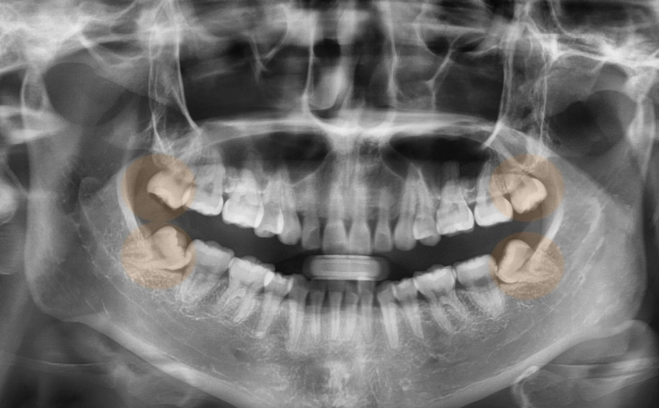

The Problem of Impaction

An impacted wisdom tooth is one that fails to fully emerge through the gums. It gets stuck. This is the core issue for most severe pain cases. The type of impaction dictates the kind of trouble you'll have.

| Type of Impaction | What It Means | Common Pain & Risks |

|---|---|---|

| Mesioangular | Tooth is angled forward, towards the front of the mouth. | Most common type. Presses hard against the molar in front, causing crowding, decay in both teeth, and gum pain. |

| Vertical | Tooth is straight but trapped beneath the gum line. | May partially erupt, creating a gum flap (operculum) that traps food and leads to infection (pericoronitis). |

| Horizontal | Tooth lies completely on its side, growing into the roots of the adjacent molar. | Often the most damaging. Can destroy the roots of the healthy second molar, causing severe, constant pain. |

| Distoangular | Tooth is angled backward, towards the rear of the jaw. | Less common, but can cause jaw pain and issues with the jaw joint (TMJ). |

I've seen patients who thought they had an earache or sinus pressure for weeks, only to find out it was a horizontally impacted wisdom tooth. The pain can radiate in surprising ways.